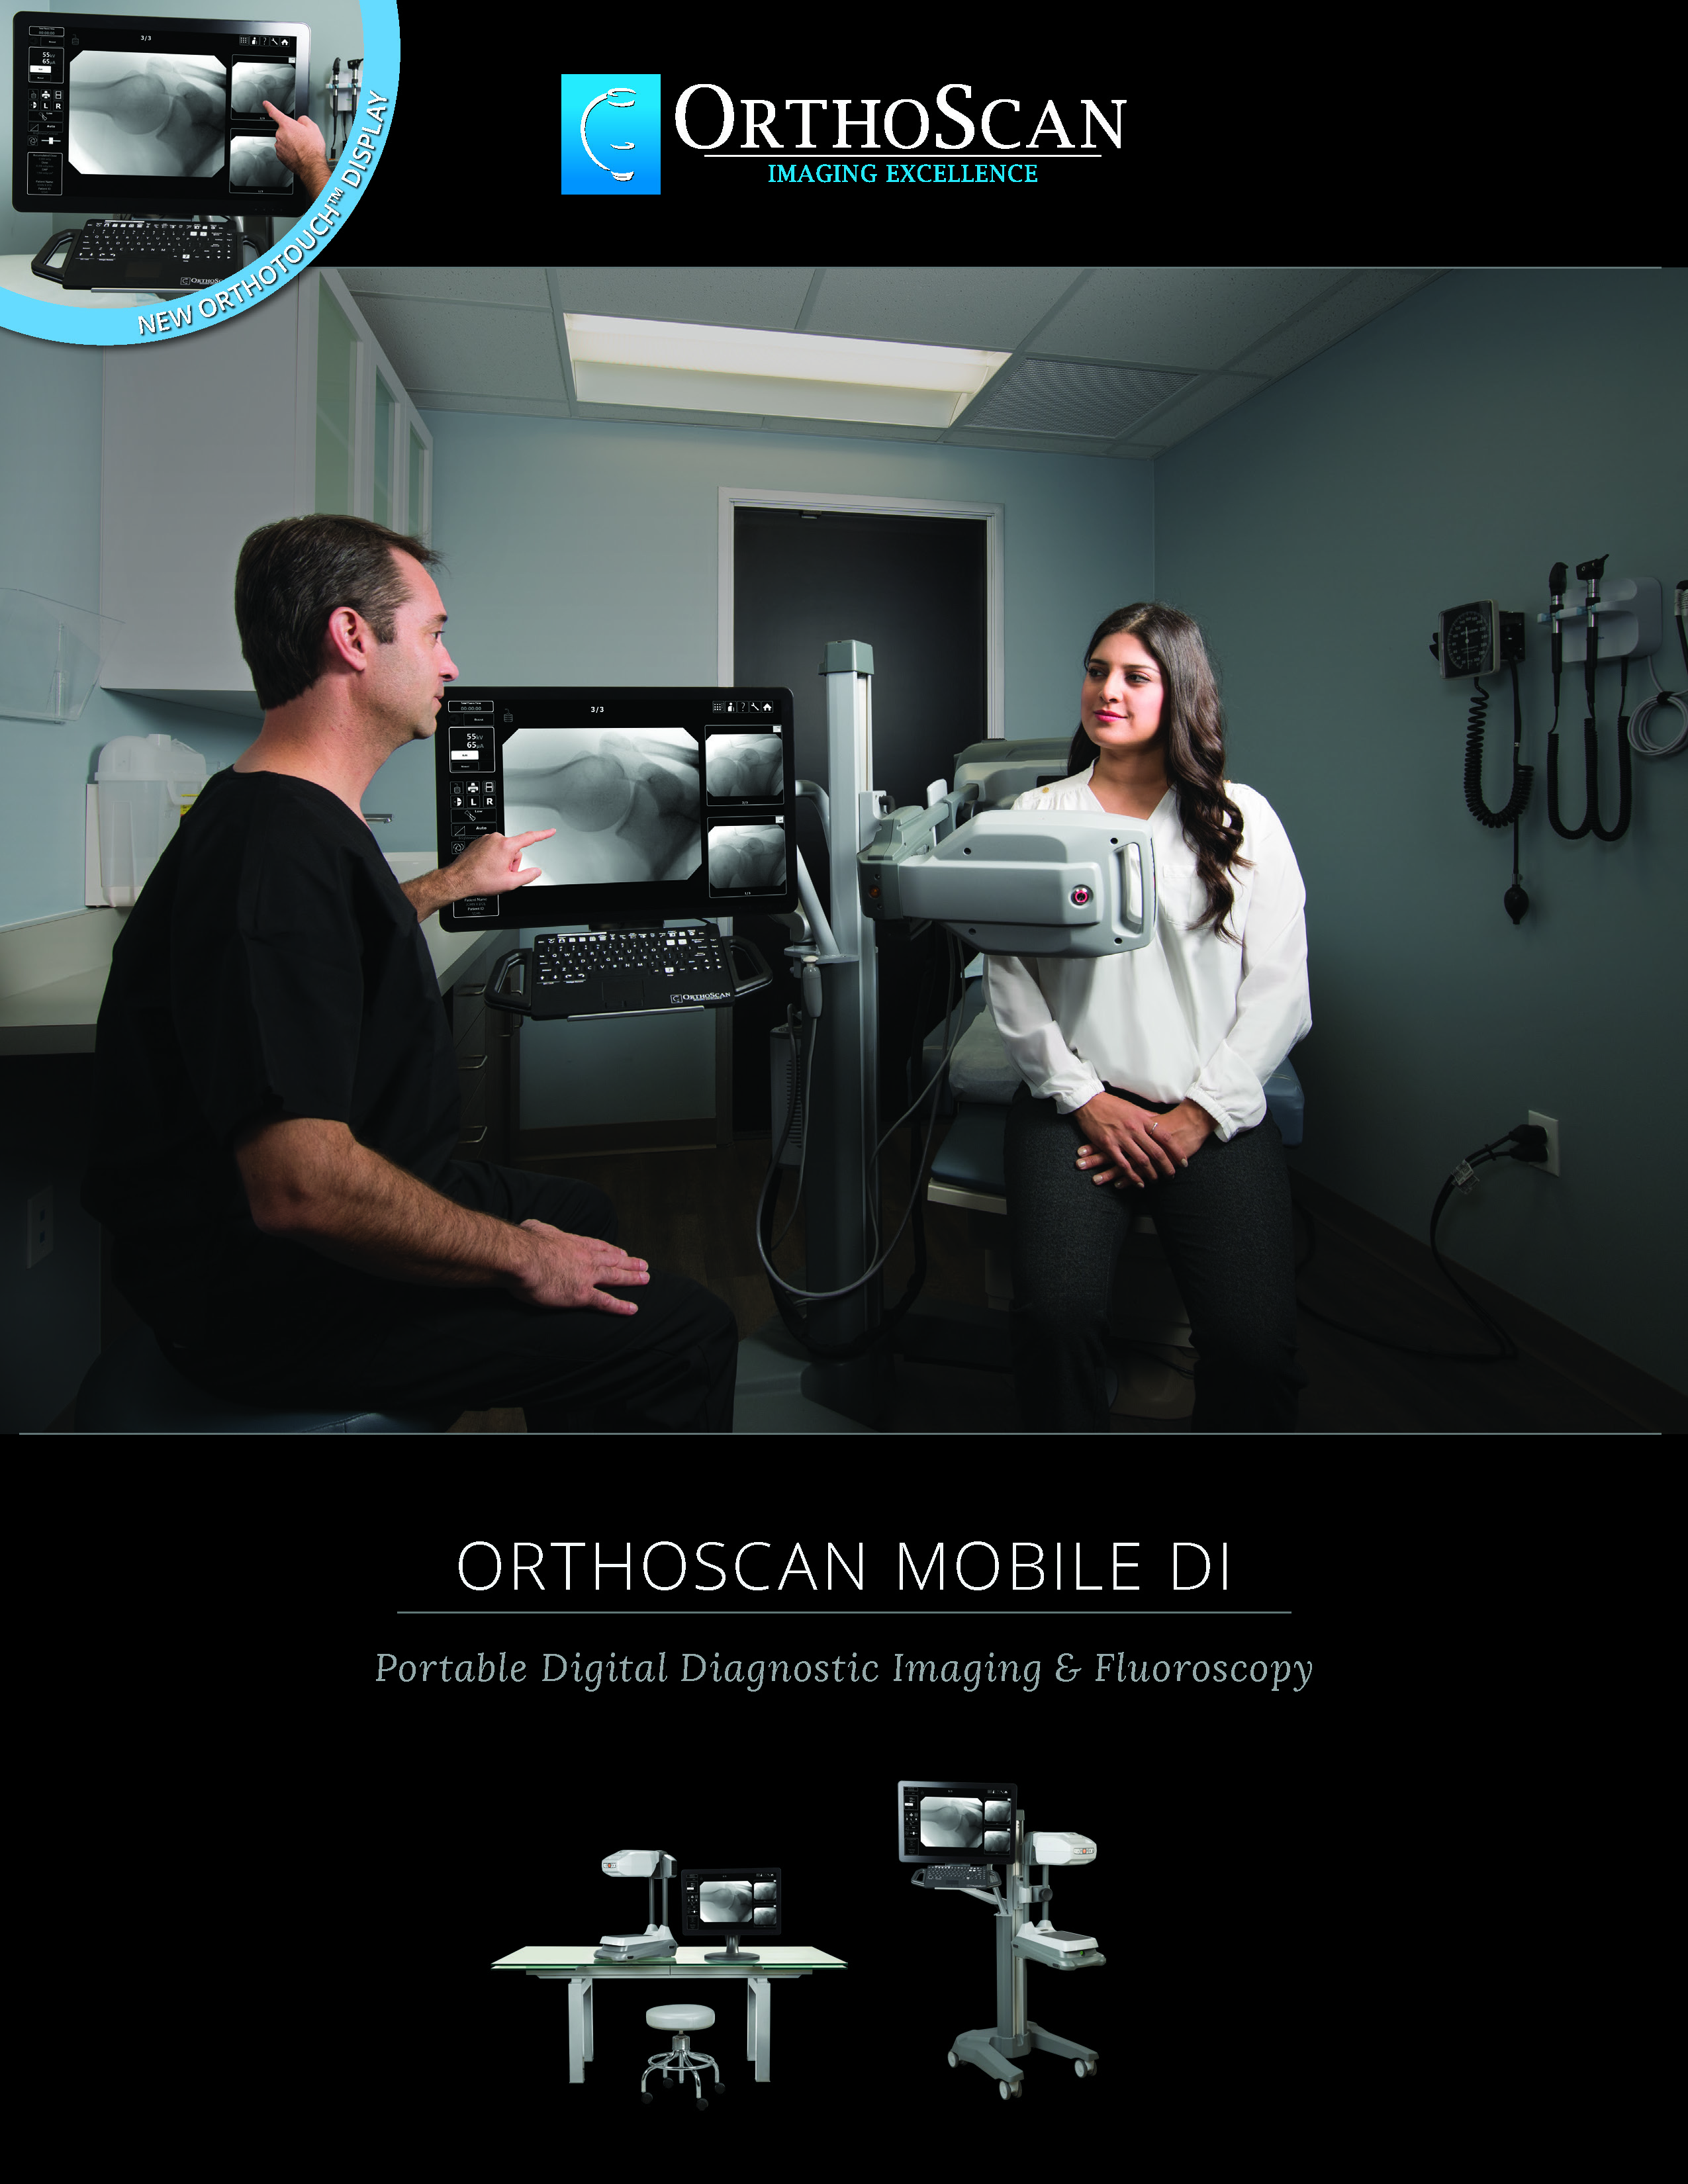

The Advanced Arthritis Relief Program (AARP) is a knee osteoarthritis (OA) treatment system that consists of fluoroscopic guided injections of Hyaluronic Acid, targeted Physical Therapy, and a special uploading Knee Brace. It’s MD, MP, and PA approved and covered by all major insurance carriers as well as Medicare.

2019 Fee Schedule & Coding Determination changes Osteoarthritis Joint Treatment & Pain Relief. After Standard of care for knee OA, MEDICARE requires patients try and fail viscosupplementation therapy prior to approving total knee arthroplasty (TKA). The AARP is this type of therapy that is approved by Medicare. It combines viscosupplementation with physical therapy and a specialized knee bracing procedure that has been delivering near perfect results.

2019 Fee Schedule & Coding Determination changes Osteoarthritis Joint Treatment & Pain Relief. After Standard of care for knee OA, MEDICARE requires patients try and fail viscosupplementation therapy prior to approving total knee arthroplasty (TKA). The AARP is this type of therapy that is approved by Medicare. It combines viscosupplementation with physical therapy and a specialized knee bracing procedure that has been delivering near perfect results.